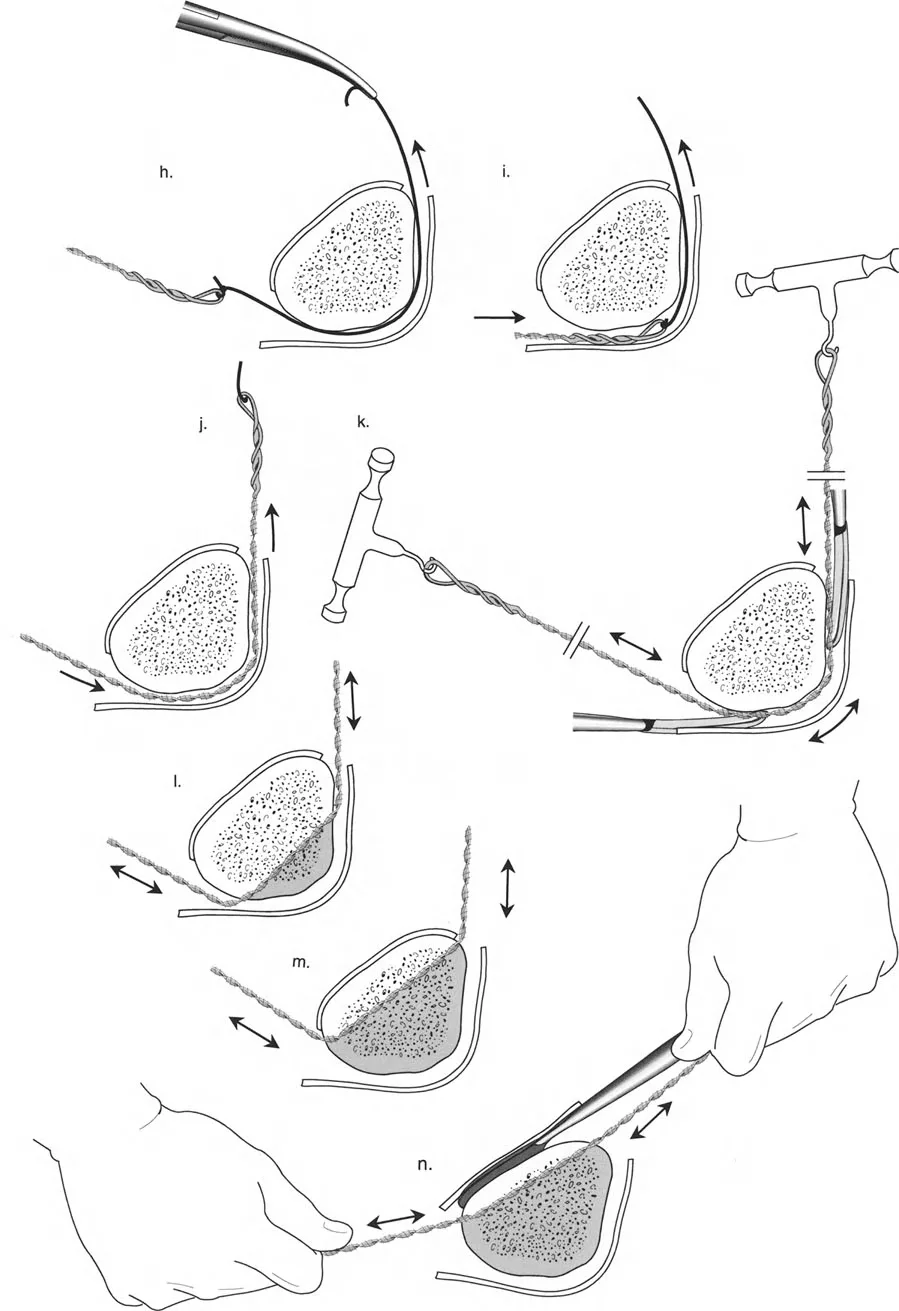

قيود الأسلاك والدبابيس في القاعدة 2

لتحقيق هذه الترجمة الضرورية والمقصودة بسلاسة باستخدام إطار دائري كامل الأسلاك، يلزم استخدام أسلاك الزيتون المعاكسة (counter-opposed olive wires). تعمل أسلاك الزيتون كقوى سحب ديناميكية، تسحب قطعة العظم على طول الحلقة أثناء فتح المفصلات. بدون أسلاك الزيتون، سيبقى العظم ثابتًا بينما تتحرك الحلقة عبر الأنسجة الرخوة، مما يسبب نخرًا شديدًا في الجلد.

على العكس من ذلك، إذا تم استخدام دبابيس نصفية (مسامير شانز)، فإنها تقيد العظم بطبيعتها بالحلقة. نظرًا لأن الدبابيس النصفية هي أذرع صلبة (مثبتة من طرف واحد بالحلقة ومغروسة في العظم من الطرف الآخر)، فإنها لا تسمح للعظم بالانزلاق على طول محور السلك. هذا يجعل أسلاك الزيتون غير ضرورية للترجمة في منشآت الدبابيس النصفية، ولكنه يتطلب من الجراح التأكد من أن الدبابيس النصفية قوية بما يكفي (عادةً دبابيس بقطر 5 مم أو 6 مم مطلية بهيدروكسي أباتيت) لتحمل لحظات الانحناء الناتجة عن الترجمة.

| تقابل الأسلاك | استخدم ما لا يقل عن سلكين زيتون متقابلين لكل قطعة إذا كنت تتجنب الدبابيس النصفية. | الأسلاك الزيتون الفردية ستسبب قصًا ودورانًا غير مرغوب فيه حول محور السلك. |

إتقان معدلات الشد: قاعدة المثلثات المتشابهة

القاعدة الذهبية البيولوجية لتوليد العظم بالشد، التي وضعها إليزاروف بعد عقود من التجارب على الحيوانات والبشر، هي معدل شد يبلغ 1 ملم يوميًا. يتم تقسيم هذا عادة إلى زيادات قدرها 0.25 ملم كل 6 ساعات لمحاكاة النمو المستمر للوحة النمو.

ومع ذلك، فإن الخطأ الشائع، الذي قد يكون كارثيًا أحيانًا للجراحين المبتدئين، هو سوء فهم أين يجب أن يحدث هذا الـ 1 ملم يوميًا.

معدل 1 ملم/يوم ينطبق بشكل صارم على القشرة المقعرة للعظم في موقع قطع العظم (الحافة الأمامية للإسفين المفتوح). نظرًا لأن الجهاز (قضيب الشد أو دعامة TSF) يقع على مسافة من العظم، خارج غلاف الأنسجة الرخوة، فإنه يتحرك على طول قوس أكبر بكثير. إذا وجهت المريض لشد القضيب بمعدل 1 ملم يوميًا، فإن العظم الفعلي سيُشد بجزء ضئيل من هذا المعدل، مما يؤدي إلى التصلب المبكر لموقع قطع العظم.

حساب معدل الشد الحقيقي

لحساب المعدل الصحيح للشد عند المفصلة، نستخدم قاعدة المثلثات المتشابهة، والتي تعتمد أساسًا على القاعدة الهندسية للدوائر متحدة